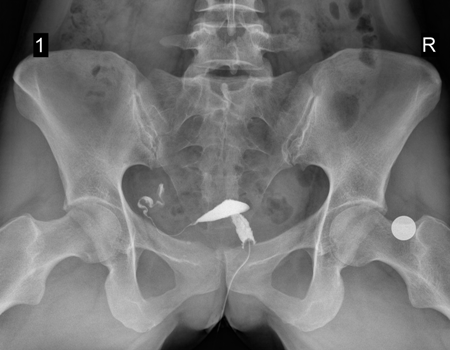

Гистеросальпингография. Непроходимость маточной трубы. Женское бесплодие

Совместно со средним медперсоналом врачом акушером-гинекологом клиники №1 Витерра Беляево пациентке выполнена гистеросальпингография: в рентген-диагностическом кабинете, в асептических условиях, после обезболивания спреем лидокаина 10%, шейка матки фиксирована пулевыми щипцами, в полость матки введен катетер для диагностической ГСГ, фиксирован манжетой. В полость матки, через проводник для диагностической гистеросальпингографии, введено 10,0 мл 76% раствора урографина.

Врачом-рентгенологом клиники №1 Витерра Беляево выполнены: укладка пациента, цифровой R-снимок малого таза (обзорный), 2 цифровых R-снимка, оценивающих распределение контрастного вещества и отсроченный (контрольный) цифровой R-снимок.

Протокол: Полость матки небольших размеров, неправильной треугольной формы, без дефектов наполнения, находится в положении антерофлексио.

Левая маточная труба тонкая, извита, проходима на всем протяжении - контрастное вещество свободно поступает в брюшную полость, распространяясь в ней по типу "дымящейся сигареты".

Правая маточная труба не контрастируется.

Тазовое кольцо сформировано правильно, симметрично. В зоне визуализации определяются тени рентгенконтрастных флеболитов, аномалия развития крестцового отдела позвоночника spina bifida posterior S1. Округлая тень артефакта размером 2,1см в диаметре - монета.

Заключение: Рентгенологическая картина непроходимости правой маточной трубы.